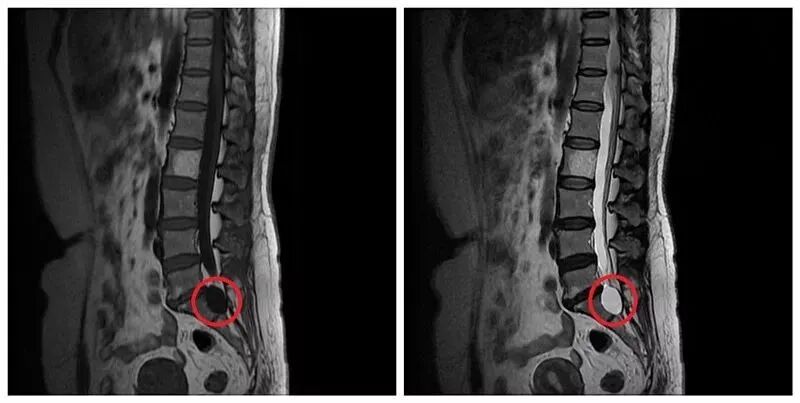

骶管囊肿是指位于骶管内的囊性病变,其本质为硬脊膜憩室或脊神经根袖的病理性扩张。

正常情况下,骶管内走形的马尾神经被一层薄薄的束膜紧紧包绕,束膜下腔为潜在的腔隙,与蛛网膜下腔不相通。由于先天发育或后天创伤、炎症等因素的作用,使局部脑脊液在静水压力增高时出现单向流动,脑脊液流入到束膜下腔,而且流入的脑脊液多于流出的脑脊液,就会使得束膜下腔逐渐扩张,从而形成囊肿。

大部分骶管囊肿没有明显的临床症状,随着囊肿体积逐渐增大,会压迫周围的马尾神经,导致神经根刺激或损害症状,骶管骨性结构也会被侵袭破坏。

大约10%~20%的患者会出现臀部、马鞍区、下肢后部、足外侧区疼痛、麻木、肌力下降,严重者会出现大、小便以及性功能障碍,称为症状性骶管囊肿。少数患者还会出现腹痛、不孕症、腿痛趾动综合征等。当出现上述症状的时候,建议到医院进行腰骶椎磁共振检查,以便及早发现骶管囊肿。